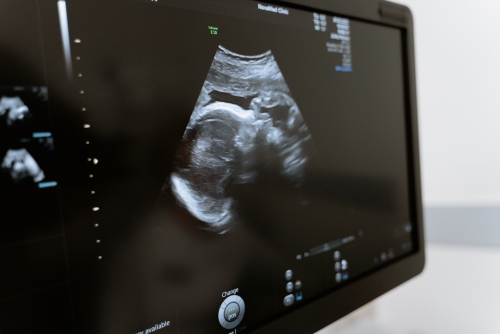

嬰兒髖關(guān)節(jié)超聲檢查,是為了檢查髖關(guān)節(jié)發(fā)育情況、測量髖關(guān)節(jié)包容間隙、觀察髖關(guān)節(jié)是否有增生、脫位、股骨頭壞死等情況。操作時(shí)一般會讓患兒取屈膝仰臥位,髖關(guān)節(jié)外展暴露,檢查者戴消毒手套,并進(jìn)行局部消毒,之后讓嬰兒處于仰臥位,雙手搭在膝關(guān)節(jié)上方,用超聲探頭對髖關(guān)節(jié)進(jìn)行檢查。

2、消毒:首先對髖關(guān)節(jié)局部進(jìn)行清潔消毒,然后鋪上無菌洞巾,并用超聲探頭對髖關(guān)節(jié)進(jìn)行探查,以觀察髖關(guān)節(jié)是否存在腫脹、積液、脫位、增生等情況;

超聲檢測2

3、探查:當(dāng)確定局部存在異常結(jié)構(gòu)時(shí),可對異常結(jié)構(gòu)進(jìn)行超聲探查,并明確具體位置;